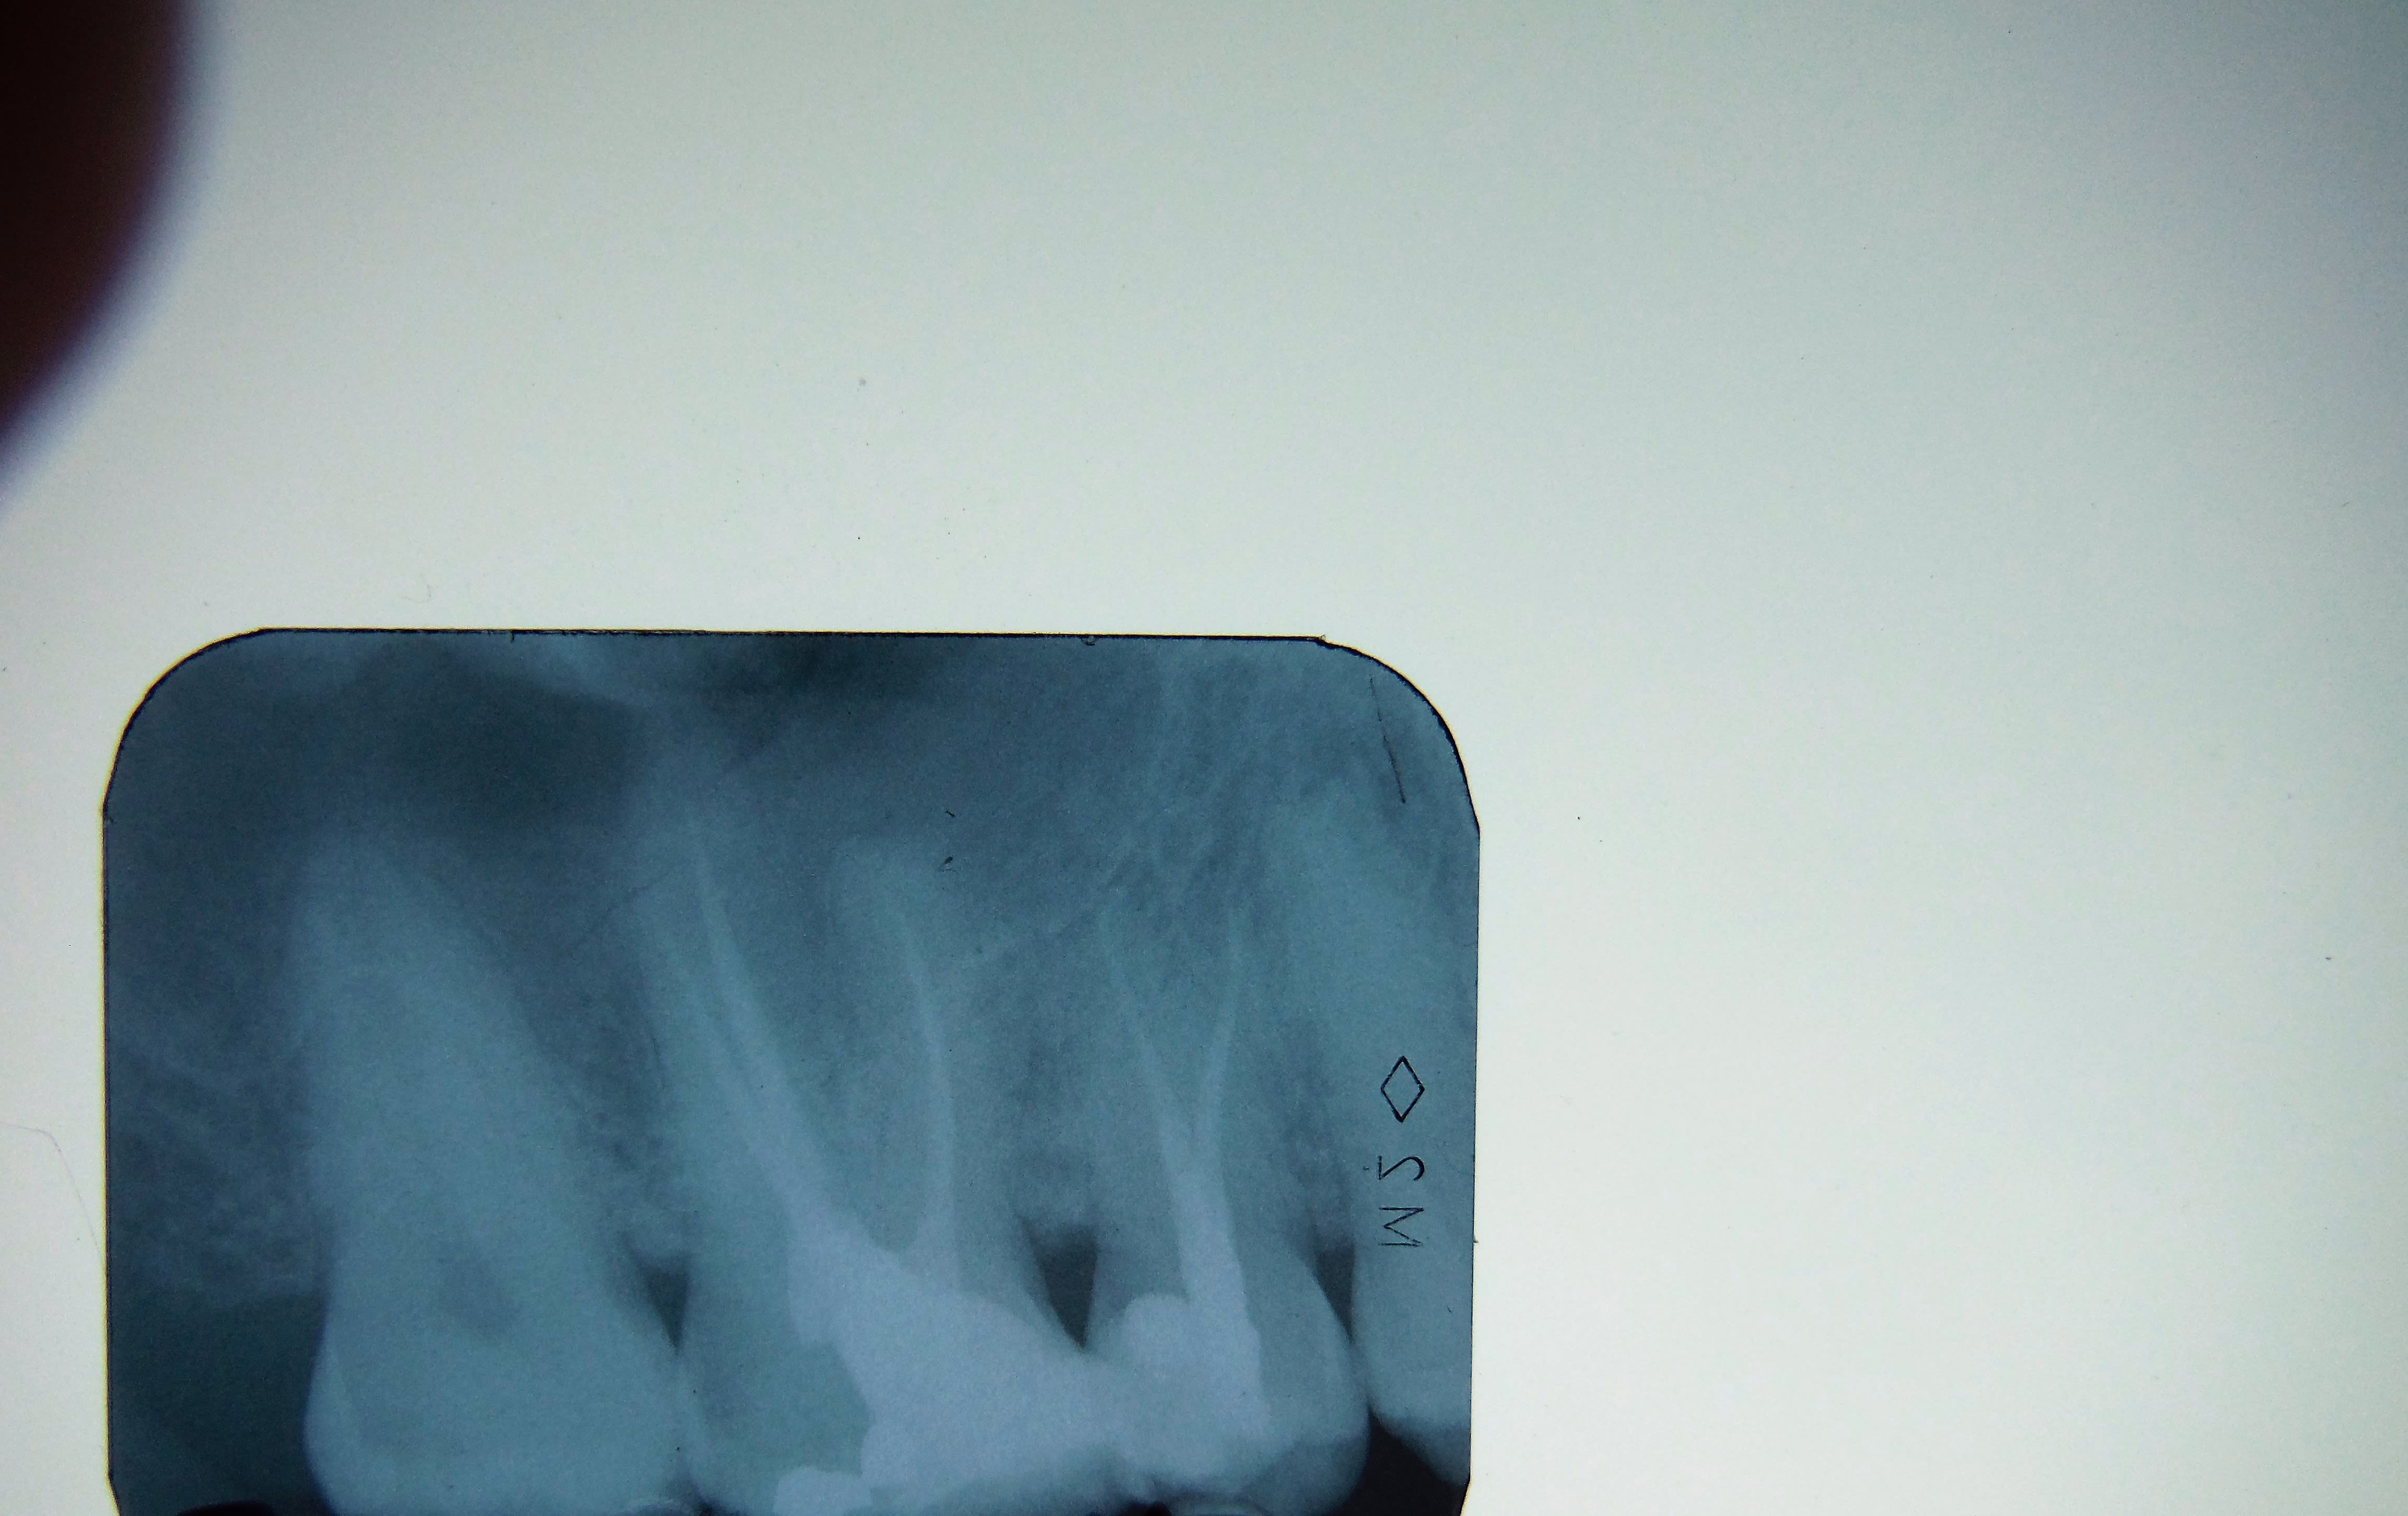

45 avec deux canaux, il m'a été impossible d'insérer une lime 8 dans le canal le plus distal.

A partir élargir la cavité d'accès, notamment afin d'enlever le bec dentinaire à l'entrée canalaire, vous avez des solutions ?

Ah! Je travaille sans aides optiques ... :) Autant vous dire que je n'ai aucune visualisation des entrées canalaires ...

De plus ton canal est probablement orienté lingualement et non distalement c est très souvent le cas de ces canaux avec split

Sans micro, j'en ai un paquet des comme ça à mon actif... Elargissement du tiers coronaire à la congé fine, ultrasons, glyde, recherche de la bifurcation au Sx ou au S1, puis R25.

Sur une radio équivalente, j'ai déjà vu une 45 à 3 canaux, le plus dur c'est l'obturation pour pouvoir insérer simultanément les 3 cônes, je ne sais plus comment j'avais fait.

5 maxillaire, un peu dans l'esprit, protapers golds

Oui voilà vulpi, j'ai déja eu des cas comme ta radio mais je n'avais pas peiné autant que sur cette 45 ... Idem je travaille au protaper

Sur ce cas, lime k 08 (06?) , k 10, k 15 puis s1, le sx est trop trapu des épaules à mon avis.

de plus je la vois triphyde ...